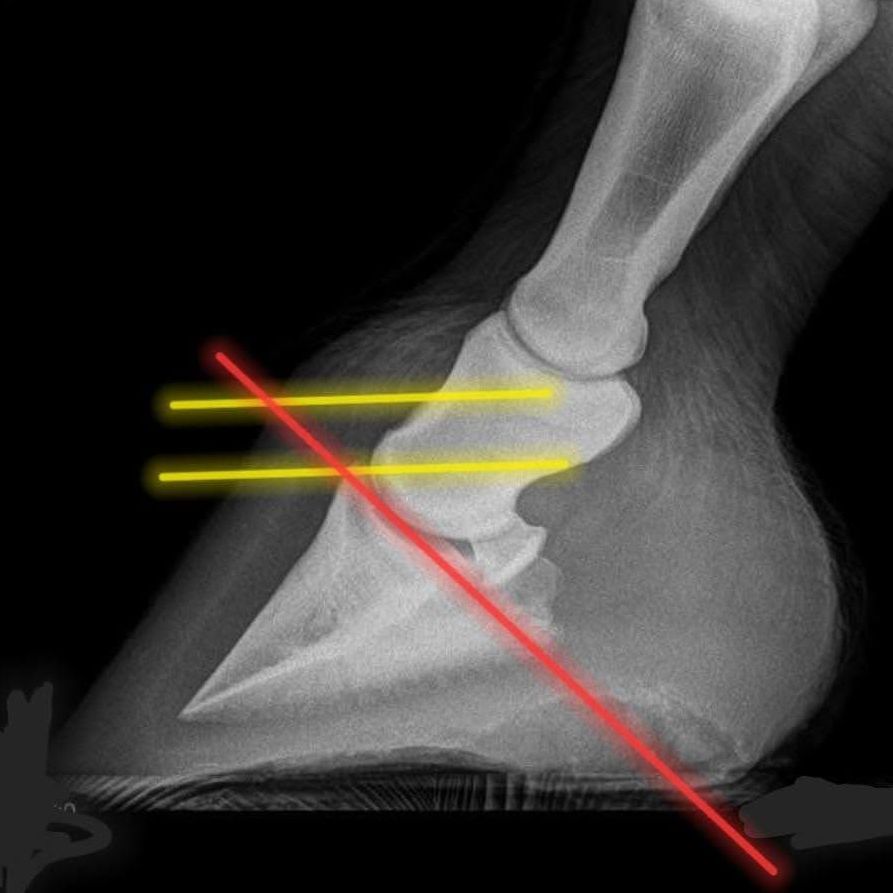

Hufbeinsenkung = Chronische Hufrehe!

gemäß Röntgenbild gekürzte Zehe

Förderung der Entwicklung der hinteren Hufhälfte für einen gesünderen Huf